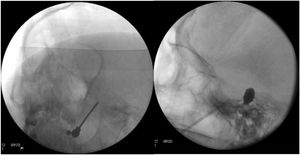

Thermocoagulation of the Gasserian ganglion. The needle inserted into the foramen ovale carries an electrode used to apply a thermal radiofrequency to the Gasserian ganglion (Fig. 4A). The patient is awoken before application of the radiofrequency, as their collaboration is needed for a sensory test that uses electric stimulation to provoke paraesthesias in order to localise the target branch. Electric stimulation may also be performed with the patient under sedation, with intraoperative neurophysiological monitoring (antidromic nerve stimulation) to locate the 3 branches of the trigeminal nerve. This procedure is not generally recommended for TN involving branch V1 due to the risk of sensory deficits affecting the cornea.

Figure 4.A) A thermal radiofrequency (thermocoagulation) electrode inserted via the foramen ovale in a patient with refractory trigeminal neuralgia of the V3 branch (Waters view). B) Cannula carrying a size 4 Fogarty balloon (shown inflated), inserted through the foramen ovale in an 84-year-old female patient with trigeminal neuralgia affecting the V2 branch (Hospital de la Santa Creu i Sant Pau).

Percutaneous balloon compression of the Gasserian ganglion. This procedure, known as Mullan’s technique, consists in the insertion through the foramen ovale of a 15 G needle carrying a size 4 Fogarty balloon; the procedure is guided by radioscopy with the patient under general anaesthesia, as their collaboration is not needed in the procedure. After placement, the balloon is inflated with contrast to a volume of 0.7−0.75 cc and pressure of 650−950 mm Hg; radioscopy shows an inverted pear or hourglass shape in Meckel’s cave (Fig. 4B). Compression is maintained for 60–120 seconds, then the balloon is deflated. Inflation of the balloon may cause bradycardia or a hypertensive crisis/emergency.